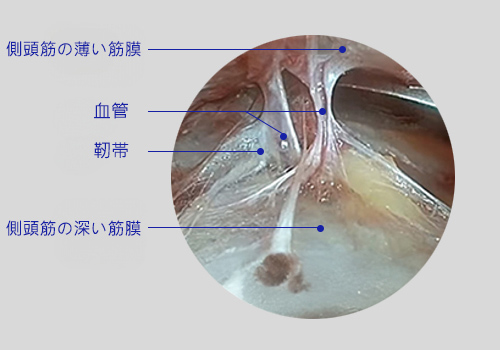

側頭筋の浅い筋膜と深い筋膜の間を、内視鏡を用いて血管や神経を避けながら安全に剥離します。

剥離後、内視鏡を使用して筋肉のみを繊細に切除し、引き上げます。